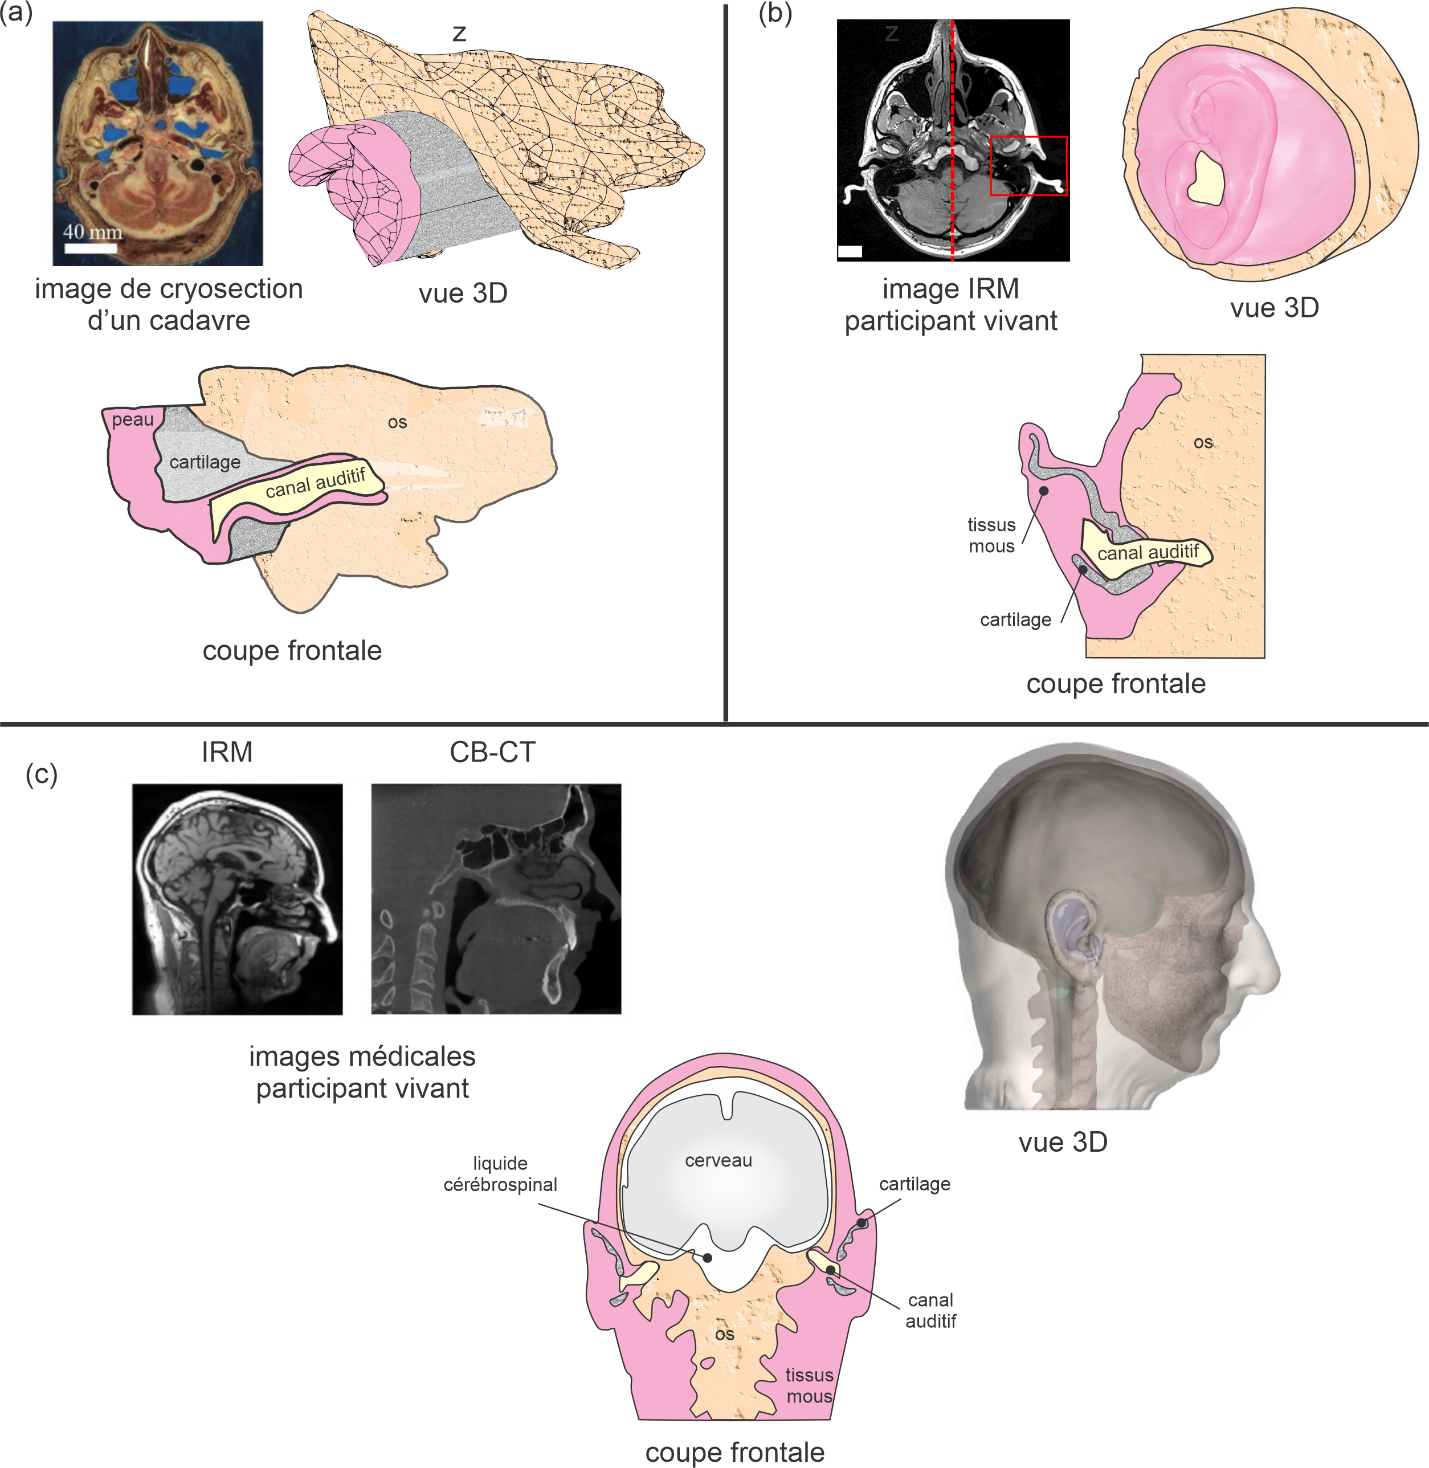

L’étape suivante consiste à prendre en compte le caractère tortueux du canal et la variation de la section droite ainsi qu’une portion des tissus environnants tels que la peau, le cartilage et l’os temporal avec un modèle 3D (Brummund et al., 2014a ; Motallebzadeh et al., 2016, 2017a, 2017b) (Figure 16a sans pavillon et Figure 16b). Dans ces derniers modèles tronqués, l’oreille externe et une partie des tissus environnants sont extraites de la tête. Afin de prendre en compte les phénomènes de conduction osseuse à travers toute la tête, l’étape ultime de réalisme consiste à considérer la tête en entier avec le canal auditif, l’ensemble de la peau, des tissus mous, cartilagineux et osseux mais aussi d’autres structures anatomiques comme le cerveau et le liquide cérébrospinal (Chang et al., 2016 ; Xu et al., 2021), les yeux, l’oreille interne, les différents types d’os (Chang, 2018) (Figure 16c). Notons que certains auteurs intègrent la peau dans les tissus mous mais considèrent le cartilage à part entière (Benacchio et al., 2020a ; Chang et al., 2016 ; Xu, 2021, 2022) alors que d’autres amalgament le cartilage et les tissus mous sous forme de cartilage équivalent, la peau étant considérée en tant que telle (Brummund et al., 2014a). Ces modèles tenant compte de la géométrie réelle des structures anatomiques nécessitent de reconstruire précisément ces structures grâce à des images médicales obtenues par cryosection en coupe d’un cadavre humain du Visible Human Project® ou Visible Korean Project (Brummund et al., 2014a ; Chang et al., 2016; Kim et al., 2014) ou directement sur des sujets humains vivants par résonance magnétique (IRM) ((Benacchio et al., 2019 ; Darkner, 2008 ; Darkner et al., 2007, 2017, 2018 ; Xu, 2021, 2022) ou encore par tomodensitométrie (CT ou CBCT) (Xu, 2021, 2022). L’acquisition d’images par IRM en oreille ouverte pose un défi du fait du bruit intense généré lors des tests. En général, les oreilles du sujet doivent être protégées à l’aide de protecteurs auditifs supra ou intra-auriculaire. Or, l’utilisation de ces protecteurs peut occasionner une déformation du canal auditif par rapport au cas où aucune occlusion n’est utilisée. On peut s’affranchir de ce problème en utilisant des séquences spéciales IRM plus silencieuses qui permettent de respecter les normes d’exposition au bruit pendant la durée du test (Benacchio et al., 2019). La combinaison d’images obtenues par diverses techniques peut s’avérer nécessaire afin de pouvoir distinguer l’ensemble des structures anatomiques. Par exemple, les structures osseuses sont difficiles à reconnaitre sur les images IRM alors qu’avec les images CT Cone-Beam ce n’est pas le cas.